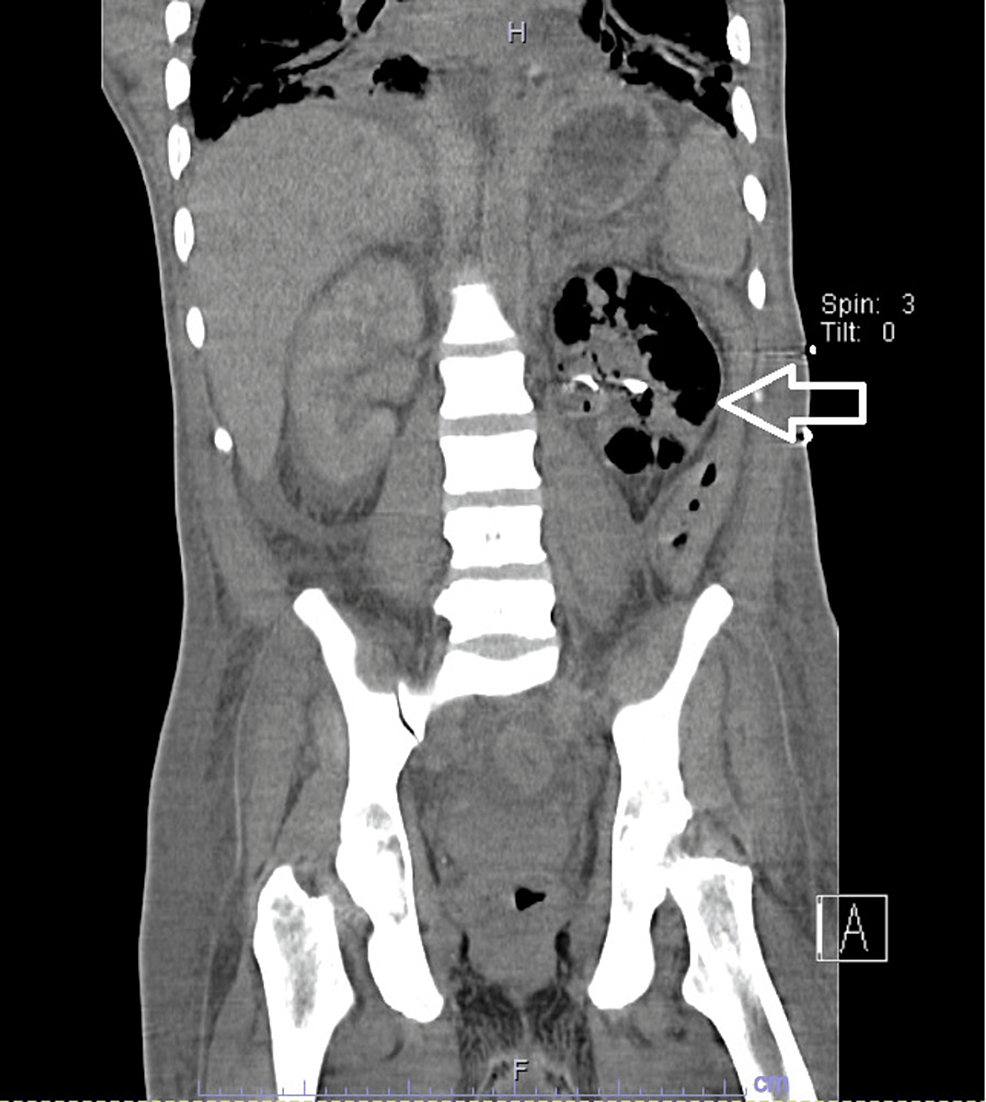

Urinoma postnephrostomy Image

Urinoma postnephrostomy Image Post Nephrostomy The nephrostomy tube drains urine from your kidney into a collecting bag outside your body. Find out how a nephrostomy is done, possible complications and ways to cope with having one. Percutaneous nephrostomy tube placement is a procedure that decompresses or provides access to the renal collecting system in. Willard goodwin in 1955 as a minimally. Blockages can be caused. Post Nephrostomy.